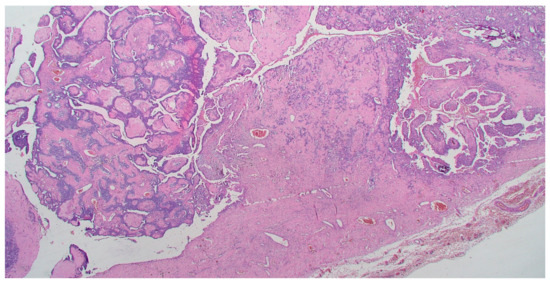

On gross pathology examination, the left ovary measured 4.5 × 3 × 2 cm, showing an intact, smooth outer surface. The cut section revealed a small unilocular cyst with an adjacent large, solid mass. The left Fallopian tube and the uterus were grossly normal. The omentum presented multiple nodules, the largest of which measured 4 cm. The resected large bowel segment showed a 5 cm nodule on the serosal surface. Histologically, the left ovary showed a serous cystadenoma, undergoing progressive transition to a serous borderline tumor and invasive carcinoma (Figure 1). The invasive part showed focal histological features of low-grade serous carcinoma (10%), but was mainly composed of a mesonephric-like adenocarcinoma (85%), showing tubular, glandular (pseudoendometrioid), sex cord-like and solid patterns (Figure 2). The tubular structures lumens contained typical eosinophilic colloid-like secretions. The nuclei were monomorphic, predominantly with vesicular chromatin and inconspicuous nucleoli. Focal lymphovascular invasion was present. There were no squamous or mucinous elements. However, a part of the neoplasm showed a chondrosarcomatous component (5%), intermingled with carcinomatous elements (Figure 3). The chondrosarcomatous component was observed also in the intestinal nodule, along with glandular and solid carcinomatous elements, infiltrating from the visceral peritoneum into the pericolic fat. The omental and peritoneal nodules revealed the same histological features as the ovarian mesonephric-like adenocarcinoma, without sarcomatous differentiation.

Figure 1. Transition from serous borderline tumor to low-grade serous and mesonephric-like adenocarcinoma. (HE, 40×).

The histological features of these tumors are peculiar. They usually show an admixture of different architectural patterns, such as tubular, glandular (variously sized), papillary, sex cord-like, slit-like, retiform and solid. The tubular and glandular patterns are the most common and often contain typical intraluminal secretions, composed of eosinophilic colloid-like material. The tumor cells show a variable shape and size, usually with a scanty eosinophilic cytoplasm and monotonous hyperchromic or vesicular nuclei [5,16]. The case herein presented showed a predominant carcinomatous component with histological features of mesonephric-like adenocarcinoma, associated with a low-grade serous carcinoma component, arising from an ovarian serous cystadenoma. These interesting histological features are in accordance with other cases in literature, demonstrating the association of mesonephric-like adenocarcinomas with other ovarian neoplasms, and may offer further proof of the possible Müllerian origin of these tumors.